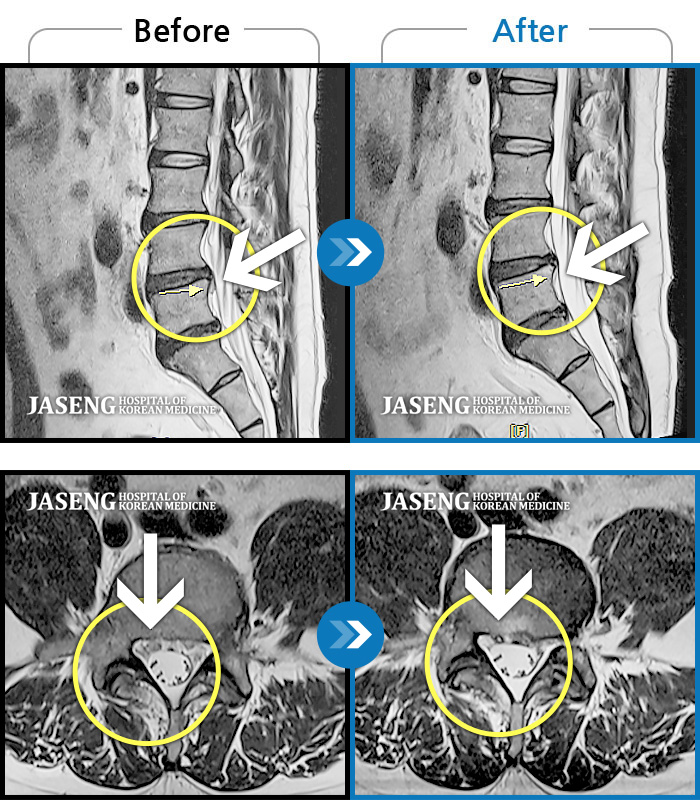

허리디스크

광주 · 김동은 원장

허리 통증과 양측 둔부부터 허벅지, 발목 부위 저리는 증상으로 내원하셨습니다.

촬영시기

2025.05.09 ~ 2025.12.18

2025.12.22